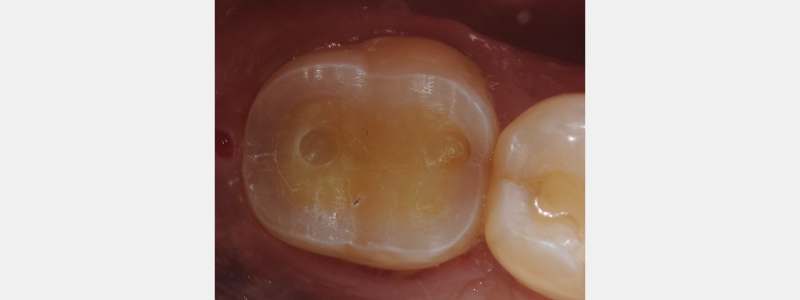

The significant lack of resistance and retention form necessitates creative ways to provisionalize and manage tooth sensitivity during the interim weeks until final ceramic fabrication and insertion. One “resistance tool” we suggest in the Restorative Design workshop is to prepare “lugs” in the occlusal surface of the tooth.

These “lugs” are 1.0 mm “pot-hole” preparations designed to provide restoration stability when seating both the provisional and final restoration. Additionally, they provide a degree of “increased surface area for the “cement” or bonding resin.

When conventional provisional cementation has minimal retention form, we must take advantage of the structural design of the natural tooth to aid in maintaining the provisional during ceramic fabrication. The photo above clearly indicates a normal tooth’s enamel and dentinal integrity. From an occlusal view, the outer enamel rim thickness can be close to 1.5 mm (when approximately 2.0 mm of occlusal reduction has occurred).